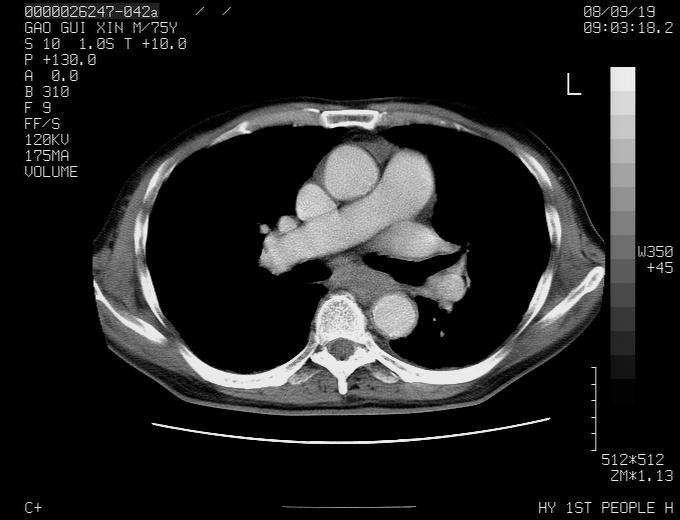

感谢各位老师的意见,左上肺病灶,我本人趋向结核,原因:左上肺见两个类圆形结节,仔细回顾4月份ct似乎原片在该处有条片状密度增高影,强化不明显。

现上传增强片,请各位老师仔细帮我看一下。

右上肺可见条索状影,并可见钙化,左上肺结节可以考虑为结核球,但气管前腔静脉后有肿大淋巴结,本人觉得左上肺结节不能排除转移瘤的可能,右上肺为陈旧性结核灶。

左肺上叶周围性肺癌并纵隔多组lnm.不可能是tb.

左肺上叶尖段瘢痕癌并纵隔淋巴结转移解释更好一些.

1)左肺上叶尖段周围型肺癌并纵隔淋巴结转移。2)冠状动脉及主动脉钙化。

左上肺周围型肺癌并纵隔淋巴结转移。纤支镜检查